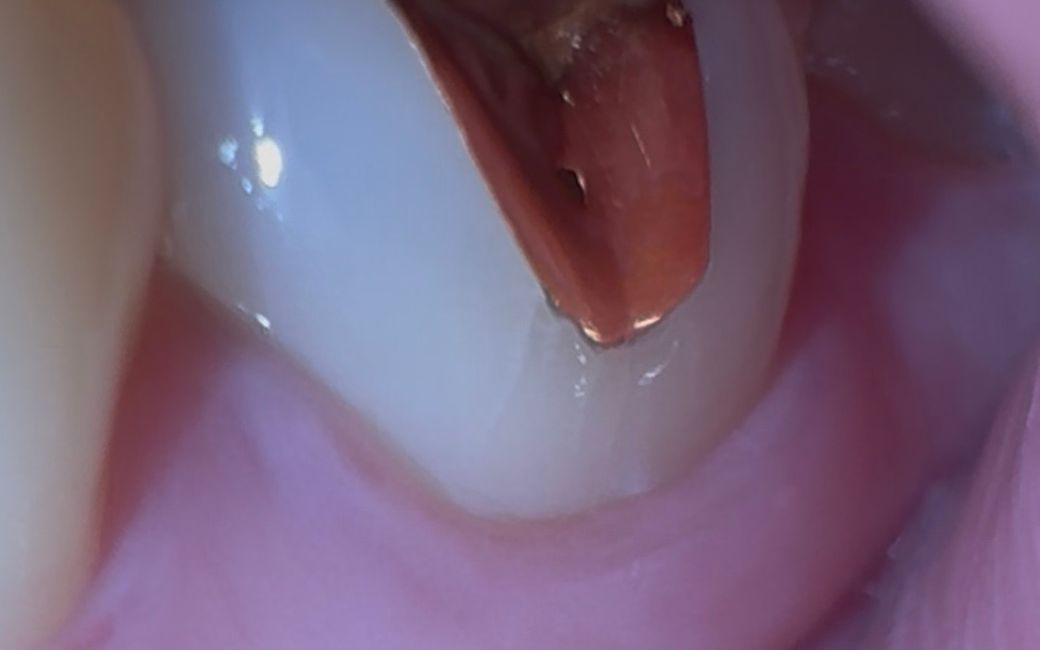

치아에 이거 크랙난건가요…ㅜㅜㅜㅜㅜㅜ

육안으로 봤을때는 안보이고 휴대폰 플래쉬켜고 동영상 초점 잘 맞춰서 찍어야 나오는데 이거 크랙일까요….. 크랙이라면 바로 치료해야되는걸까요?? 일주일 전 치과2개 갔을때는 다 멀쩡하다고 하셨는데.. 크랙인가요..?정말..??ㅠㅠㅠ

크랙은 아니고 금 인레이가 시간이 지나면서 틈이 생긴거 같습니다. 크게 문제가 잇어 보이진 않습니다.

사진으로 봤을 경우에는 치아에 미세한 크랙이 있어 보입니다. 크게 문제가 되지는 않지만 불편감이 있거나 금이 더 커질수 있다면 추가적인 치료가 필요할수 있습니다.

자세한 확인을 위해서 치과에서 진료를 받아보는 것을 권유드립니다.

1. 금인레이 주변으로 약간 실금이 보이긴 하는데 이게 치아 내부까지 진행된 크랙일지는 확신할 수 없네요

2. 금인레이는 크랙을 유발하기도 합니다